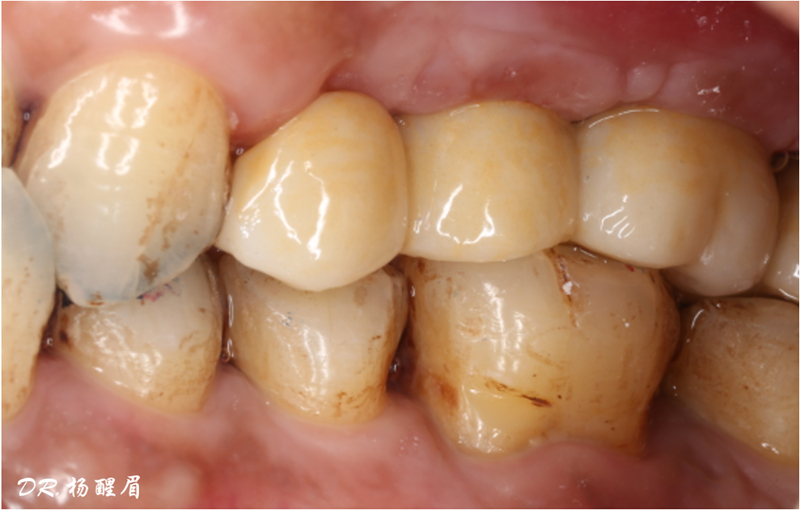

檢查:患者14、15、16、17缺失,無紅腫潰瘍,牙齦情況良好,口腔衛(wèi)生狀況良好。

診斷:14、15、16、17缺失

修復完成